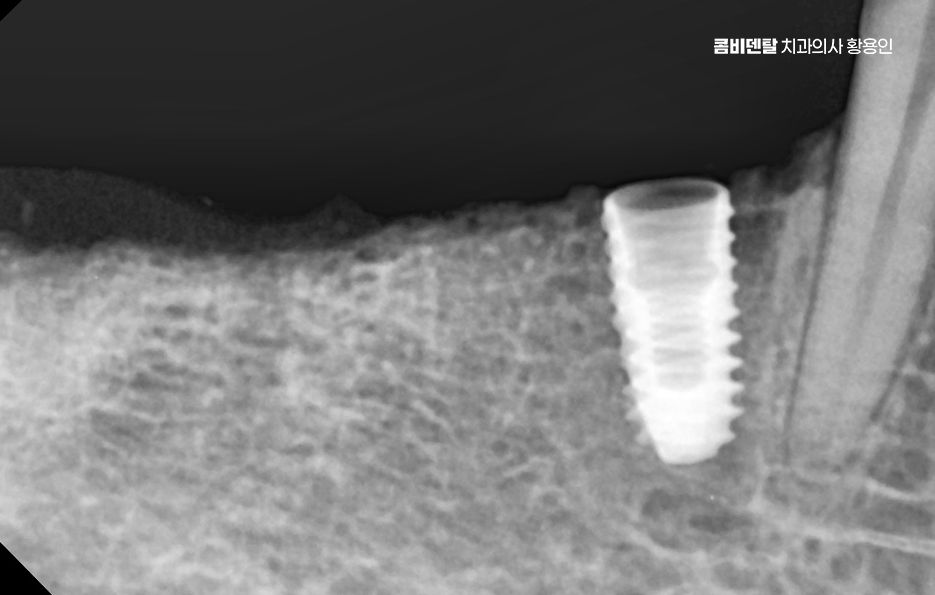

두 번째는 뼈이식을 단독으로 먼저 시행할 것인지, 임플란트 식립과 동시에 병행할 것인지를 결정해야 하는데 뼈 소실 정도가 심하지 않은 경우라면 동시에 진행할 수도 있지만, 뼈가 너무 얇거나 신경과 가까운 부위라면 3~6개월 정도의 치유기간을 두고 뼈이식만 먼저 시행한 뒤, 뼈가 자리 잡은 후에 임플란트를 식립하는 2단계 방식이 안전한 선택이 되는 거예요.